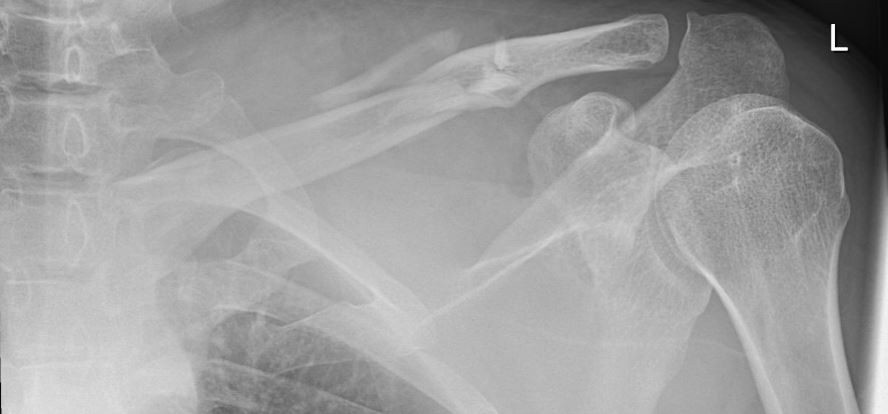

Figure 1: Radiographic imaging of the affected left shoulder region: Slightly displaced,

comminuted midshaft clavicle fracture.